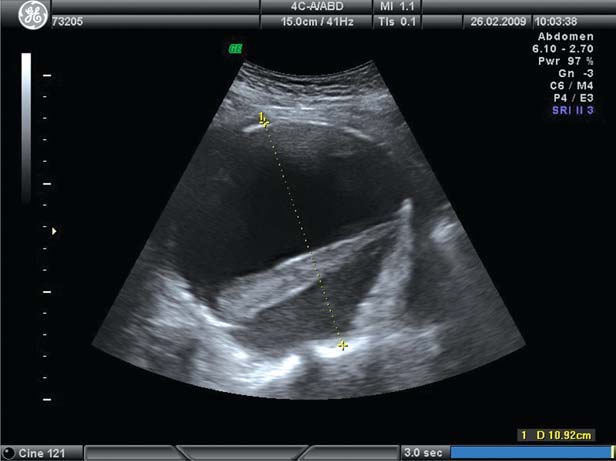

Olbrzymi tętniak aorty brzusznej uwidoczniony podczas wykonywania USG jamy brzusznej i miednicy

Jednoczesna operacja olbrzymiego tętniaka aorty brzusznej i raka esicy – opis przypadku i przegląd piśmiennictwa

W pracy przedstawiono przypadek pacjenta leczonego chirurgicznie z powodu olbrzymiego tętniaka aorty brzusznej i raka esicy. U chorego podczas jednej operacji wycięto tętniaka aorty brzusznej i raka esicy. Przebieg pooperacyjny był niepowikłany, a pacjent wyszedł do domu w 8. dobie po zabiegu operacyjnym.